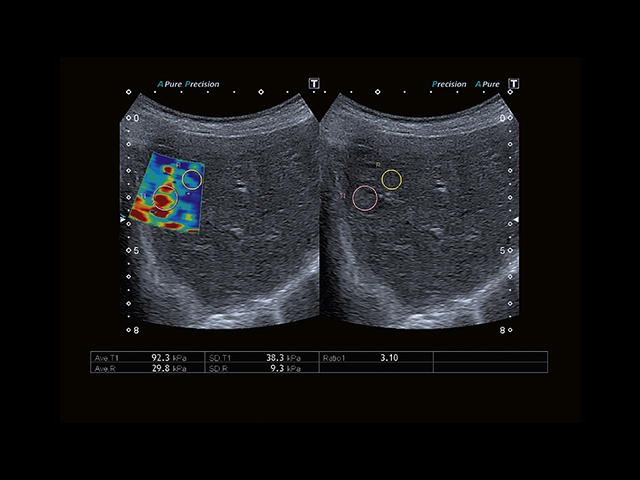

Обновленная версия легендарного УЗ-сканера. Стационарный аппарат экспертного класса Aplio 500 Toshiba NEW, визуализирует анатомические структуры в высоком разрешении. Модель позволяет выявить микрокальцификаты, новообразования, нарушения в работе сердца, сосудов и мышц. Присутствует функция виртуальной эндоскопии, 4D-сканирования, эластометрии тканей, УЗИ с контрастированием. За повышение качества изображения отвечают технологии ApliPure и Superb Microvascular Imaging. Первая задействует возможности пространственного и частотного кодирования, формирует цельный визуальный ряд с сохранением клинических маркеров. Вторая улучшает отображение микрососудистого русла, используя доплеровский эффект. Модель оснащена 21-дюймовым монитором, имеет 4 активных порта. Возможно подключение педиатрических, интраоперационных, лапароскопических и чреспищеводных датчиков.

Эластография:

Компрессионная

Эластография сдвиговой волной/Эластометрия:

Компрессионная эластография: